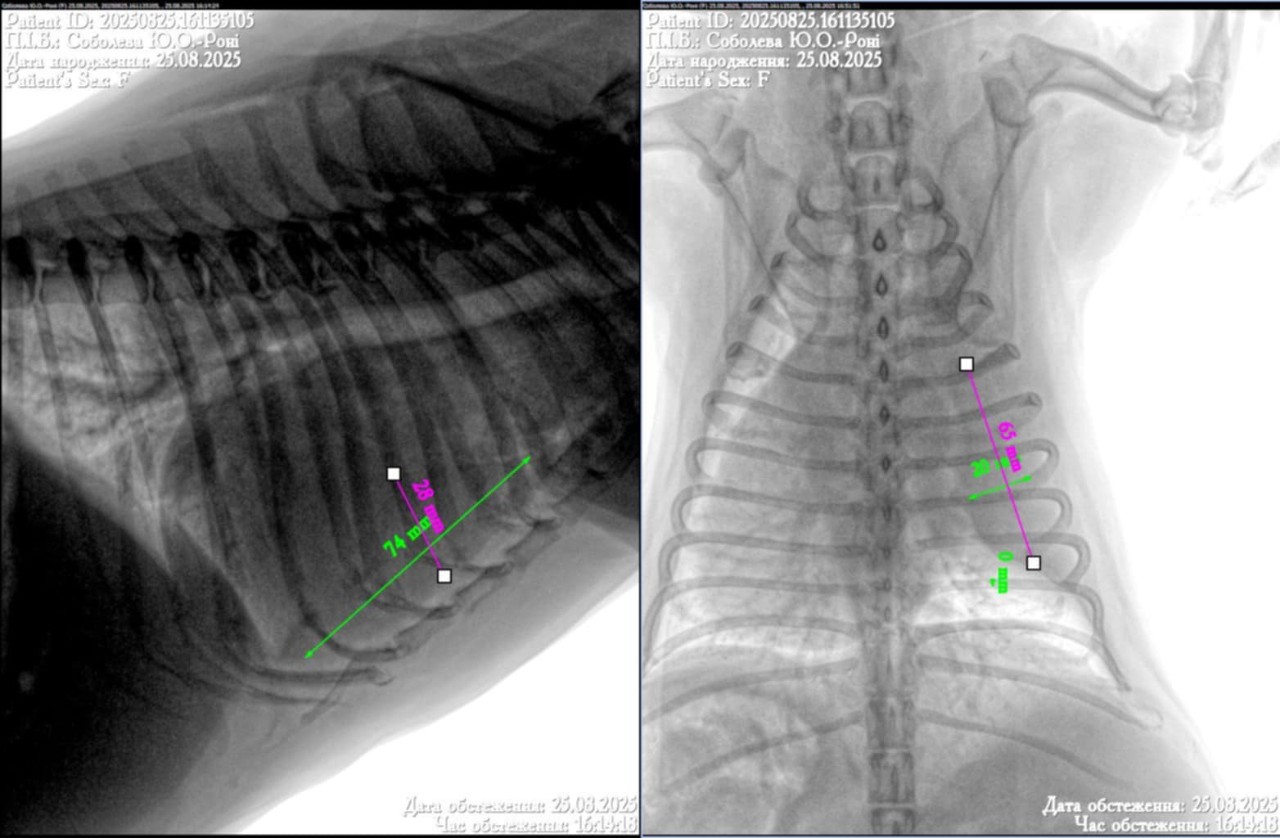

Добрый день уа. Врачи у меня неординая просьба к вам, так как мы находимся прифронтовой зоне и сейчас нет возможности выехать мы не можем помочь своему четверолапому. У него кашель, сердце исключили, сказали искать проблему в легких, рентген нам получилось сделать, а вот описание ренгена нет, ветгруппы нам не помогли. Если это возможно, помогите нам пожалуйста! Очень просим помощи, спасибо.